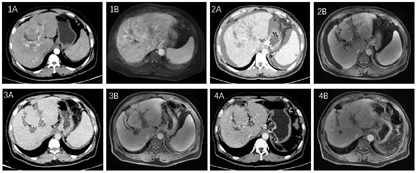

患者有丙肝肝硬化病史,甲胎蛋白升高,有典型的影像学表现,临床诊断为肝癌。由于患者弥漫性肝癌合并门静脉癌栓,经我科评估为不可切除。给予保肝治疗后患者肝功能较前好转,Child评分5分、A级。根据《原发性肝癌诊疗指南(2022版)》推荐意见,给予"T+A"方案(即阿替利珠单抗注射液1 200 mg+贝伐珠单抗注射液1 000 mg静脉注射,1次/3周),同时行肝动脉化疗泵植入术,术后经肝动脉泵给予肝动脉持续灌注化疗(hepatic artery infusion chemotherapy,HAIC),化疗方案为FOLFOX4方案。治疗3个周期后,于2022年3月1日行磁共振增强扫描肝胆胰脾(肝脏特异性对比剂),结果提示肝脏病变范围缩小,腹水较前增多;肝硬化、门静脉高压(图2)。2022年3月4日行上腹部增强CT检查,结果提示肝脏病变及门静脉癌栓范围较前缩小,肝硬化较前加重,门静脉海绵样变性、门静脉高压基本同前,腹水较前增多(图2)。实验室检查:甲胎蛋白降至15.1 µg/L。第4次HAIC治疗后患者肝动脉化疗泵泵体周围软组织出现感染,遂拆除肝动脉化疗泵,未再行HAIC治疗。"T+A"治疗5次后复查,于2022年5月10日行磁共振增强扫描肝胆胰脾(肝脏特异性对比剂),结果提示肝脏病灶及门静脉癌栓消失,门静脉血栓致门静脉闭塞,门静脉海绵样变性;肝硬化、门静脉高压;腹水较前减少(图3)。2022年5月11日行上腹部增强CT检查,结果提示肝脏病变及门静脉癌栓消失,肝硬化,门静脉海绵样变性,门静脉高压基本同前,腹水较前减少(图3)。实验室检查:甲胎蛋白降至3.4 µg/L。在治疗过程中,患者耐受性良好,未出现Ⅲ级及以上不良反应。患者治疗过程中影像学变化见图1。

经多学科协作诊疗讨论,认为患者病情完全缓解,建议继续行"T+A"治疗巩固疗效。患者因自身经济原因未继续行"T+A"治疗。2022年6月患者无明显诱因出现黑便、呕血,考虑食管胃底曲张静脉破裂出血,于当地医院行食管曲张静脉套扎治疗。后患者就诊于我院,完善术前评估,由于患者合并中度脾功能亢进,且呈进行性加重趋势,遂于2022年7月4日行腹腔镜脾切除加贲门周围血管离断术,术后患者恢复良好。2022年8月11日复查上腹部增强磁共振成像,2022年8月12日复查上腹部增强CT,均未见肿瘤复发征象(图4)。2022年8月25日再次在内镜下行食管胃底曲张静脉套扎治疗。

患者恢复良好,未再出现呕血、黑便。2022年11月25日复查上腹部增强磁共振成像,2022年11月27日复查上腹部增强CT,均未见肿瘤复发征象,复查甲胎蛋白在正常范围内。经评估,患者肝癌治疗后完全缓解时间已超过半年,目前患者一般状态良好。